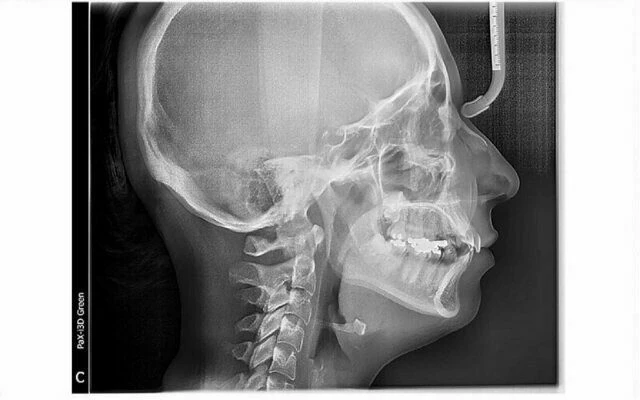

Kỹ thuật chụp Phim Cephalometric và các loại Cephalogram

Để có được một Cephalogram chất lượng, việc tuân thủ các quy ước và sử dụng thiết bị Cephalometric phù hợp là rất quan trọng. Theo quy ước, khoảng cách từ nguồn Tia X đến vật thể trên mặt phẳng đứng dọc thường là 5 bước. Khoảng cách từ mặt phẳng dọc giữa đến Cassette phim có thể khác nhau tùy vào máy nhưng phải luôn giống nhau cho từng bệnh nhân.

Phim Cephalometric mặt bên: Mặt phẳng đứng dọc giữa của đầu theo quy ước được đặt cách tiêu điểm của ống chụp phim 60 inches về phía bên trái (quy ước của châu Âu là phía bên phải) vật thể so với phim. Tia X trung tâm trùng với Trục transmeatal (chẳng hạn như thanh giữ tai của Cephalostat). Trong hầu hết trường hợp, khoảng cách từ mặt phẳng dọc giữa đến phim được giữ hằng định, thường là 7 inches (18cm). Đầu của bệnh nhân được đặt sao cho Mặt phẳng Frankfort song song với sàn nhà và răng nằm ở vị trí cắn khớp bình thường, môi thả lỏng.